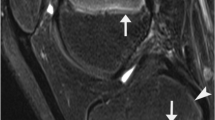

(A) A radial-sequence MR image of the hip of a 20-year-old basketball player taken at the 2 o’clock position is shown. (B) The diameter (d) of the femoral head, through the center of the head-neck axis, and the distance from a line orthogonal to the diameter to the lateral-most extension of the epiphysis (e) is measured. The epiphyseal extension is defined as e/d. (C) The measurement of the alpha angle on this same MRI slice is shown.

Our key measurement variables were epiphyseal extension measured on radial-sequence MRI at each position of the cranial hemisphere from 9 o’clock (posterior femoral head-neck junction) to 3 o’clock (anterior head-neck junction) and the corresponding alpha angles (Fig. 1) [14, 19]. A proton-weighted radial sequence on a 3.0 Tesla MR system (Siemens, Erlangen, Germany) was used for evaluation of morphologic features of the proximal femur [18]. The radial planes were rotated clockwise in 30°-intervals around and perpendicular to the femoral neck axis resulting in seven hour-defined measurement points (Fig. 2). Epiphyseal extension is calculated as follows: (1) the head-neck axis is drawn through the center of the femoral head to the medial femoral head, (2) a line orthogonal to this axis is drawn starting at the medial femoral head toward the clock position being measured, (3) the distance between this line and the physeal extension is measured, parallel with the head-neck axis, and (4) this distance (e) is divided by the femoral head diameter (d) to express epiphyseal extension as a ratio (Fig. 1B). The alpha angle was measured according to the technique described by Nötzli et al. [14]. Briefly, this is the angle between the femoral neck axis and a line connecting the femoral head center with a point, where the femoral head contours leaves a best-fit circle around it (Fig. 1C, Fig. 2).

(A) Radial-sequence MRI planes are perpendicular to the femoral head-neck axis. (B) Positions are defined clockwise with the 12 o’clock position being superior and 3 o’clock position being anterior; 3 h = 3 hours; 6 h = 6 hours; 9 h = 9 hours; 12 h = 12 hours. (Published with permission from Siebenrock KA, Ferner F, Noble PC, Santore RF, Werlen S, Mamisch TC. The cam-type deformity of the proximal femur arises in childhood in response to vigorous sporting activity. Clin Orthop Relat Res. 2011;469:3229–3240.)